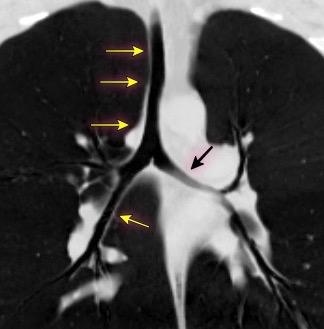

Normal

Espacio normal

Densidad baja uniforme del espacio. Pared interna de BPI-BI visible.

BPI sin alteraciones Ángulo carinal normal

Crecimiento AI

Ganglios Quiste broncogénico

Ganglios subcarinalesl Ángulo carinal normal

Sarcoidosis

Müller NL et al. Subbcarinal Lymph Node Enlargement: Radiographic Findings and CT Correlation. AJR 1985